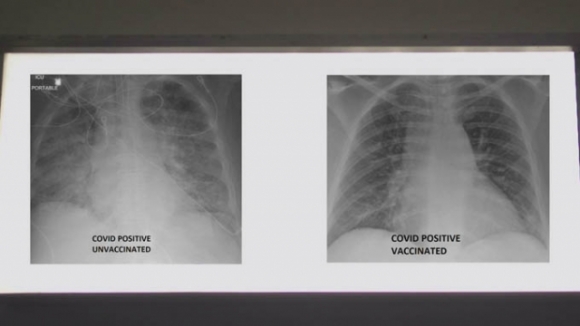

So sánh ảnh chụp phổi của bệnh nhân COVID-19 không tiêm và có tiêm vaccine. Ảnh: KSDK

Để xem vaccine COVID-19 có thể giúp ích như thế nào, Bệnh viện SSM Health đã cung cấp hai bức ảnh chụp X-quang phổi của 2 bệnh nhân COVID-19 cho đài KSDK. Trong hai người này, một người đã được tiêm vaccine COVID-19, một chưa chưa tiêm.

Tiến sĩ Kamel đã xem phim chụp X-quang và giải thích chất màu trắng trong phổi mà bạn nhìn thấy chính là tác động của virus. Đó có thể là vi khuẩn, chất nhầy hoặc dịch tiết, tiến sĩ nói.

Tuy nhiên, tiến sĩ Kamel đã phân tích về sự khác biệt có thể thấy trên phim chụp X-quang.

Ông cho biết khi nhìn vào hình chụp X-quang của người chưa được tiêm vaccine COVID-19, ông đánh giá đây rất có thể một bệnh nhân cần được hỗ trợ.

"Họ chắc chắn ít nhất cũng cần oxy và đôi khi họ cần nhiều hơn thế. Họ có thể cần dùng máy thở hoặc được đặt nội khí quản, dùng thuốc an thần và về cơ bản là hỗ trợ sự sống", tiến sĩ Kamel nói.

Còn nếu bạn nhìn vào hình ảnh của người đã tiêm vaccine, bạn sẽ thấy nhiều màu đen hơn. Tiến sĩ Kamel giải thích: Khi phổi chứa đầy không khí, nó sẽ có màu đen trong phim X-quang. Như vậy, bức ảnh này có nhiều màu đen hơn ảnh trước.

Chủ nhân của phim X-quang này mắc COVID-19 dù đã được tiêm vaccine - một trường hợp hiếm khi xảy ra. Chỉ dưới 1% những người được tiêm vaccine bị nhiễm COVID-19.

Đối với những người đã tiêm vaccine mà không may nhiễm bệnh, họ thậm chí có thể không cần đến bệnh viện.

Nếu họ cần tới bệnh viện, hầu hết đều không cần phải vào ICU hoặc cần hỗ trợ sự sống, tiến sĩ Kamel cho biết. Các trường hợp ngoại lệ bao gồm những người có bệnh nền từ trước hoặc những người bị suy giảm miễn dịch.